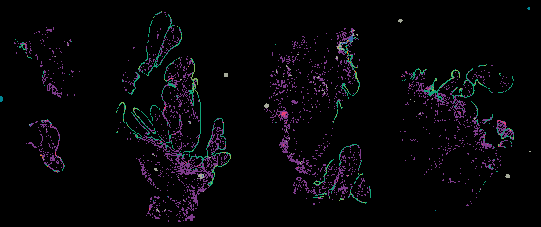

Ovarian STIC Spatial Transcriptomic Data from GeoMX and Multiplex Imaging